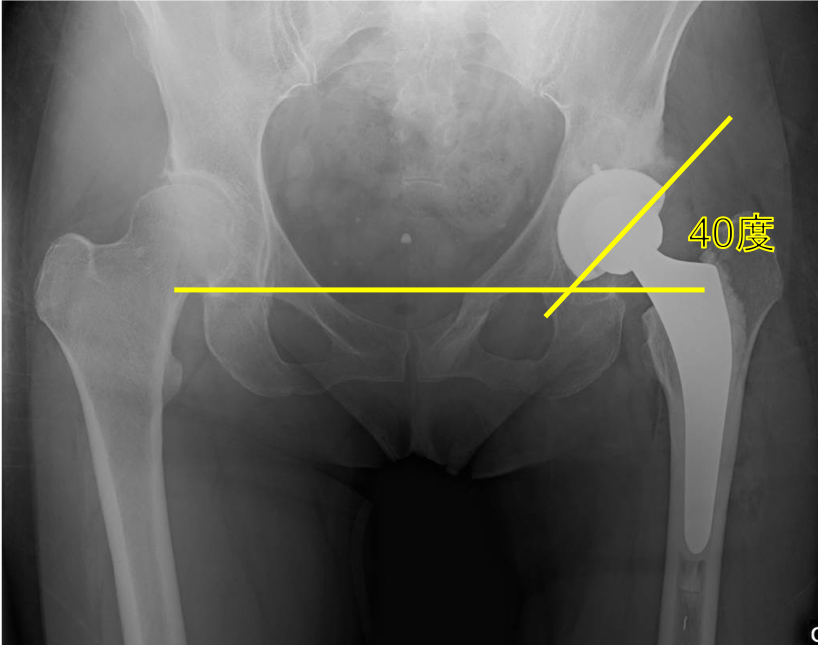

そのためにはインプラントの正確な設置も非常に重要となります。 股関節のカップの設置の理想は、正面から見て、外側に40度、側面から見て、前側に15度の角度がついているものが脱臼リスクの最も少ない理想の設置と言われています。

理想的なインプラントの設置のために、手術前の計画(3次元テンプレート)から、手術中(オーダーメイドの骨モデルやガイド、透視装置の使用)にも様々な工夫を行ない、理想的なインプラントの設置、そして“forgotten joint”を目指しています。